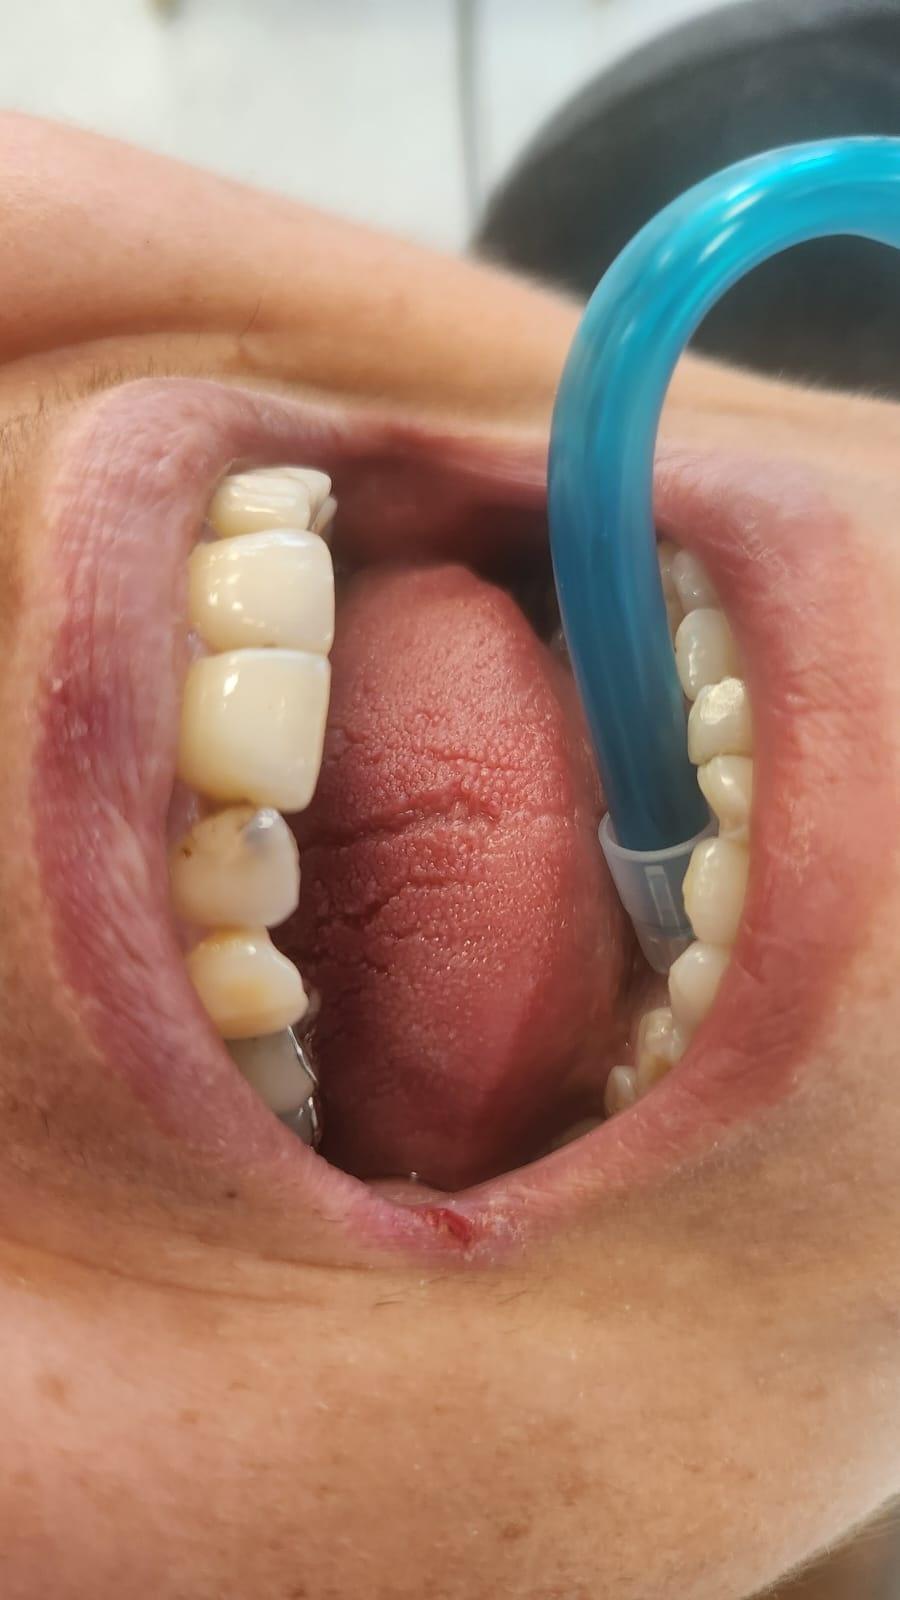

Clinica LUY ESTHETIC ART dispune de ultimele tehnologii in domeniul stomatologic si ofera solutia tratamentelor endodontice, pentru a incerca sa salveze un dinte care a fost distrus in proportii mari. Specialistii nostrii efectueaza acest tratament in mod corespunzator, pentru a evita aparitia altor complicatii ce implica interventii mai complexe: rezectia apicala sau riscul de a pierde dintele.

La Clinica LUY ESTHETIC ART tratamentul endodontic poate fi efectuat pe durata mai multor sedinte, doar cand chisturile dezvoltate sunt medii. Tratamentul nu este dureros deoarece se realizeaza sub anestezie. Pe langa talent, cunostinte medicale, dar si meticulozitate, acest tratament, presupune folosirea unei aparaturi performante: